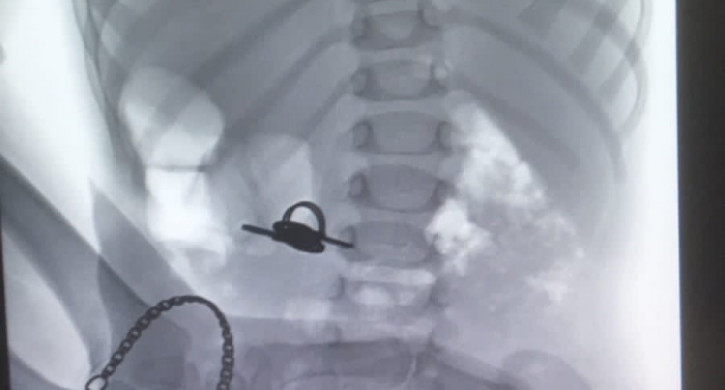

В ЧОДКБ из желудка ребенка извлекли ключи, передает корреспондент Агентства новостей «Доступ» со ссылкой на больницу.

Сообщается, что полуторагодовалый малыш проглотил связку ключей. Врачи-эндоскописты извлекли инородный предмет из желудка ребенка.